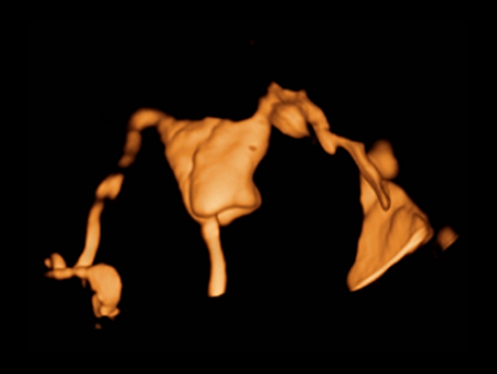

ImĂĄgenes clĂnicas